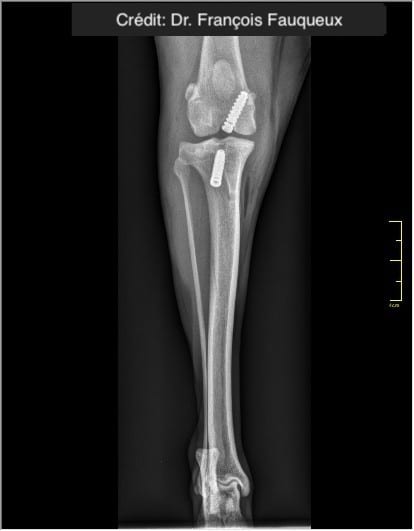

Radiologické snímky

Mimokloubní stabilizace, která je dlouhodobě pevná, bez uzlů a zvlnění.

V případě ruptury kraniálního zkříženého vazu umožňuje ExtraTape® extraartikulární rekonstrukci co nejblíže izometrii původního vazu, čímž rychle a trvale stabilizuje koleno bez uzlů a zvlnění, což je slabina tradičnějších technik extraartikulární stabilizace. Ty jsou zde nahrazeny pevným ukotvením kosti pomocí interferenčního šroubu.